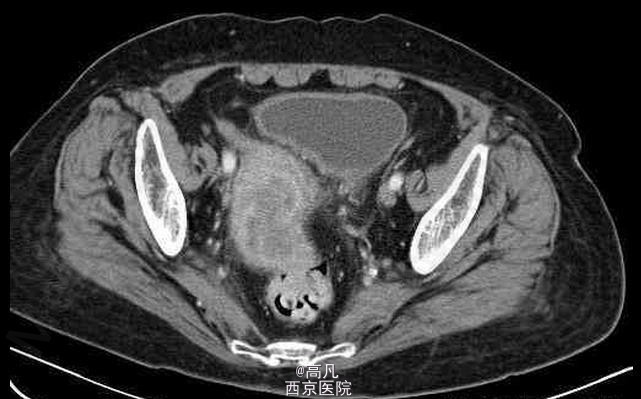

临床一例子宫内膜癌

子宫内膜癌

女,70岁,因近日来阴道不规则出血前来就诊

不规则阴道出血,常为少量至中等量的出血,有稀薄的白色分泌物 辅查CT,MRI,CT表现常可见宫体不均匀增大, MRI示子宫内膜增厚,T2WI上内膜信号不均,部分可见宫内低信号连接带中断

子宫内膜癌 处理:以手术为主,配合化疗及放疗